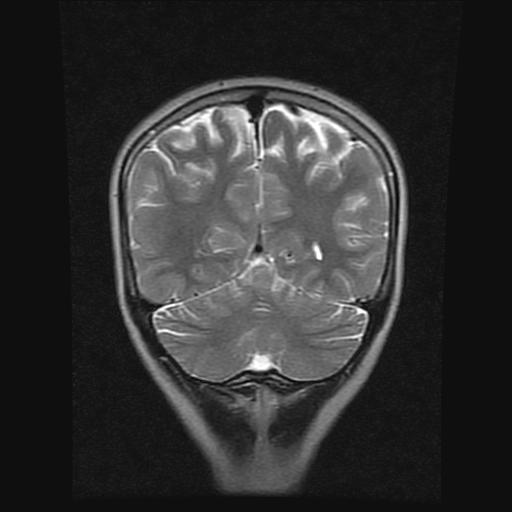

9岁女孩,三岁时诊断为癫痫,一直服丙戊酸钠,现患者一般情况良好,家长复查核磁片,看能否停药..

巨脑回

未见异常信号灶.

未发现异常信号。